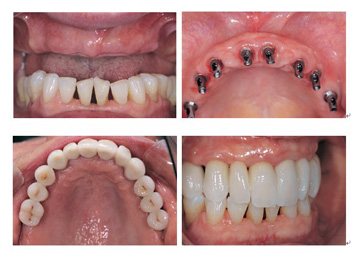

广州越秀圣贝口腔门诊部连锁采用目前先进的种植之一。耐用持久,世界上颗种植牙已正常使用40年。运用广泛,适用于牙齿缺损、牙列缺损、全口无牙。品 质坚硬,基台坚固,稳定性强,大限度恢复正常咀嚼功能,咬合力达到正常牙的98.98%;生物相容性极好,口感良好,无任何异物感,临床适应症高于 98.98%,不良反应低于0.02%;美学效果良好,大限度还原真牙形态;定位准确,无其他损伤,种植体直接嵌入牙槽骨,不损伤相邻牙齿; 有效防止牙齿缺失后牙槽骨继续萎缩。经过一段时间后,种植体就会与周围的骨组织发生骨结合,并为牙齿修复体如牙冠、固定桥、部分活动义齿或全口义齿提供坚固的固位力。